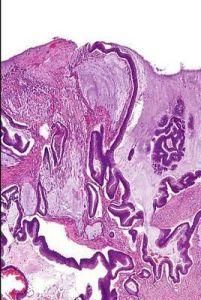

當 癌細胞分泌粘液較明顯時,稱為粘液腺癌.乳頭狀型1例,癌細胞核 異型性明顯,核仁大, 核分裂像易見.實體型2例,分化低異型性高

2、粘液腺癌(潰瘍型、縮型、菜花型、乳頭狀、息肉型)細胞

3、粘液腺癌、隆起型粘液腺癌、潰瘍型粘液腺癌細胞